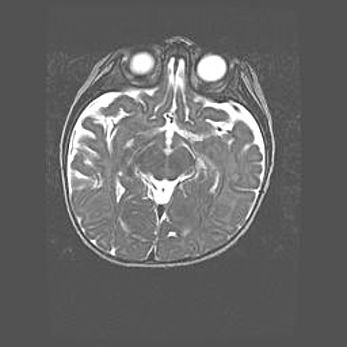

Множественные кисты обоих полушарий головного мозга, наибольшая из них в правой затылочной области. Ассиметричная атрофическая гидроцефалия.

Возраст: 7 месяцев

Вес: 5660 г

Пол: мужской

Окружность головы: 41,5 см

Срок гестации: 28-29 недель

Кисты головного мозга развиваются в результате многоочаговых некрозов вещества мозга и возникают вследствие перенесенной перинатальной инфекции, менингитов, энцефалитов, асфиксии, родовой травмы, расстройств мозгового кровообращения различного генеза. Образованию кист в веществе головного мозга плодов и новорожденных способствуют такие факторы, как высокое содержание в нем воды, недостаточная (или отсутствие) миелинизация и слабая астроглиальная реакция на повреждение.

Кисты могут сочетаться с гидроцефалией и другими поражениями головного мозга.